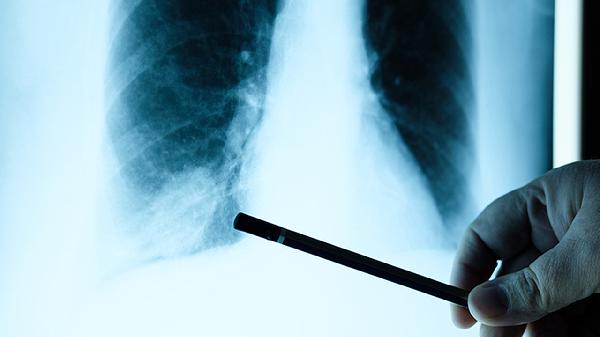

肺部膨脹不全可通過體位引流、呼吸訓(xùn)練、藥物治療、支氣管鏡治療、手術(shù)治療等方式恢復(fù)。肺部膨脹不全可能與支氣管阻塞、肺部感染、胸膜疾病、神經(jīng)肌肉疾病、外傷等因素有關(guān),通常表現(xiàn)為呼吸困難、咳嗽、胸痛等癥狀。

頑固性肺不張或合并膿胸時需行胸腔閉式引流或肺葉切除術(shù)。手術(shù)可徹底清除病灶,但創(chuàng)傷較大,術(shù)后需加強(qiáng)呼吸道管理。術(shù)前需評估心肺功能,術(shù)后早期下床活動預(yù)防深靜脈血栓,定期復(fù)查胸片觀察肺復(fù)張情況。